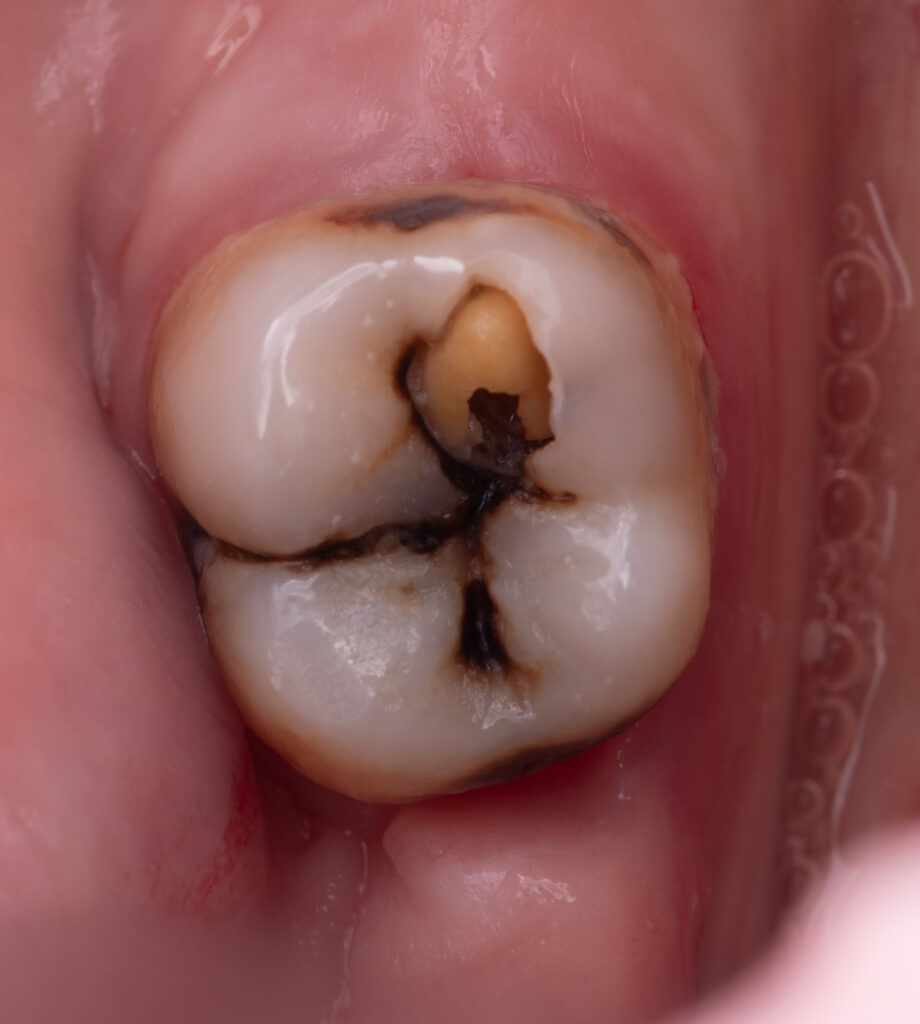

We started the treatment with a periapical radiograph to confirm the absence of any periapical changes and to assess the root canal lumen.

A cold test was performed, which confirmed a vital pulp.

Next, caries-infected dentin (CID) was removed using a caries detector. The mesio-lingual wall was reduced due to the lack of dentin support.